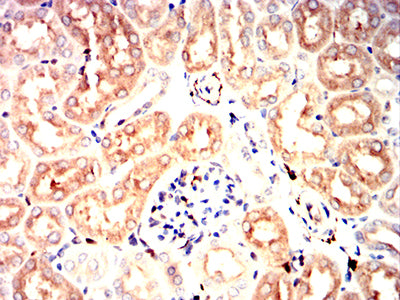

Immunohistochemical analysis of paraffin-embedded mouse kidney tissues using UCHL1 mouse mAb with DAB staining.

Immunohistochemical analysis of paraffin-embedded rat kidney tissues using UCHL1 mouse mAb with DAB staining.